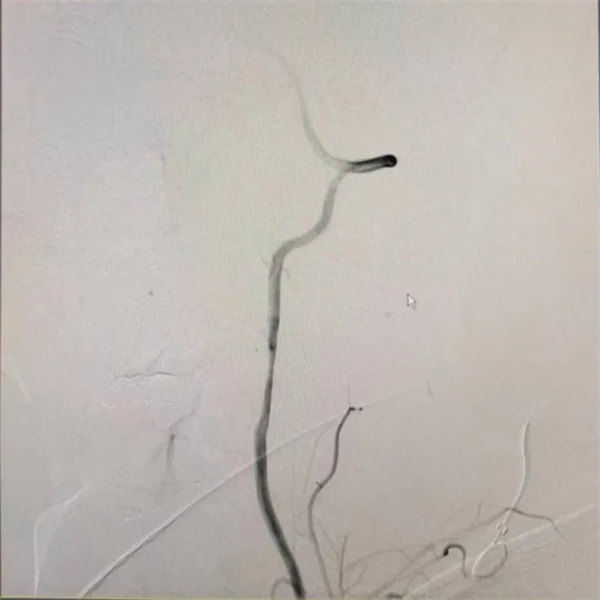

為進一步明確夾層的位置、長度以及血流情況并進一步治療,神經內三科團隊為患者進行腦血管造影檢查明確椎動脈夾層,血流良好,不需要血管內治療。經積極雙聯抗血小板治療,何先生頭暈及雙下肢無力等癥狀基本消失。出院后繼續雙聯抗血小板治療,1月后再進行復查,明確夾層修復情況。